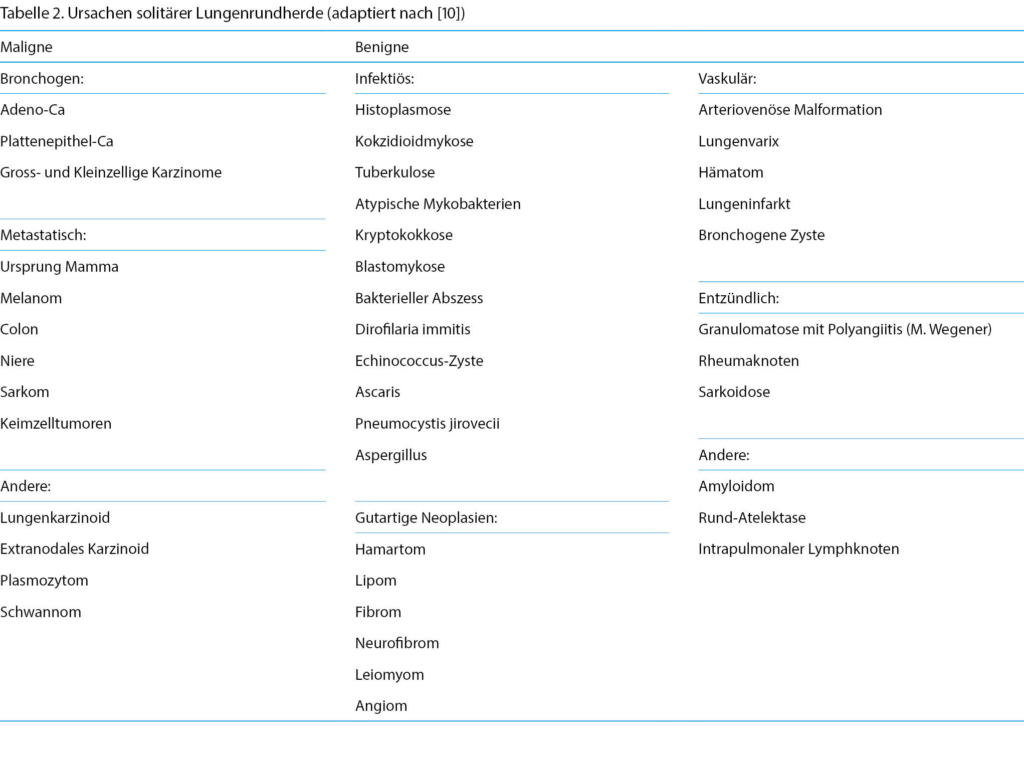

Unter den meist radiologisch/zufallsbefundlich entdeckten Lungenrundherden finden sich nach Resektion und pathologischer Aufarbeitung ca. 50 % gutartige Befunde. Die inzidentellen Lungenrundherde (Röntgen, CT) sind oft wenig symptomatisch. Radiologisch benigne, aber keineswegs verlässliche Zeichen sind die glatte Oberfläche, eine Stielbildung, ein erhöhter Kalkanteil, ein Fettgewebsanteil, ein stabiler Verlauf über die Zeit sowie das Fehlen von Retraktion, Spikulae, Gefässnachweis oder dickwandigen Zysten.

Unter den Karzinomen aber hat das Lungenkarzinom [6] mittlerweile die höchste Mortalität [7], wobei auch Nie-Raucher (< 100 Zigaretten auf Lebenszeit) zu rund 25 % betroffen sind. Entsprechend bedürfen solide und subsolide, solitäre (Tabelle 2) oder multiple Lungenrundherde mindestens ab sechs Millimeter im Durchmesser [8] gemäss Risikoeinschätzung einer mindestens leitliniengerechten Beobachtung oder histologischen Sicherung [9].

Als Differenzialdiagnose zum Bronchuskarzinom muss an eine pulmonale Metastase, eine chronische Pneumonie oder auch einen benignen Lungentumor gedacht werden. Benigne Lungentumoren gehen von Bronchien oder Lungenparenchym aus, und es fehlt eine Destruktion, Invasion oder Metastasierung [5, 11]. Unter den eigentlichen Lungentumoren sind die benignen leider selten und nur für zirca 1–3 % verantwortlich.

Histologisch erfolgt die Einteilung der benignen Lungentumoren nach dem Ursprungsgewebe (epithelial: Papillome, Adenome. Mesenchymal: v.a. Chondrome. Mischformen und nicht zuordenbare Tumoren), wovon das Hamartom am häufigsten ist. Diagnostisch ist die minimalinvasive Thoraxchirurgie das Mittel der Wahl. Ein abweichendes Vorgehen ist nur bei Grössenkonstanz über zwei Jahre, sehr kleinem Durchmesser und sichergestellter Verlaufsbeobachtung mittels CT Thorax gerechtfertigt.

Bezüglich Procedere wird entschieden über eine Kontrolluntersuchung versus Resektion (interventionell, thorakoskopisch, chirurgisch offen). Obwohl zystische Läsionen radiologisch eher benignen Befunden entsprechen, muss beachtet werden, dass auch Tumoren und Lymphome zystisch degenerieren können (z.B. Thymom, M. Hodgkin/ Lymphome, Keimzelltumoren, neurogene Tumoren, mediastinale Lymphknotenmetastasen).